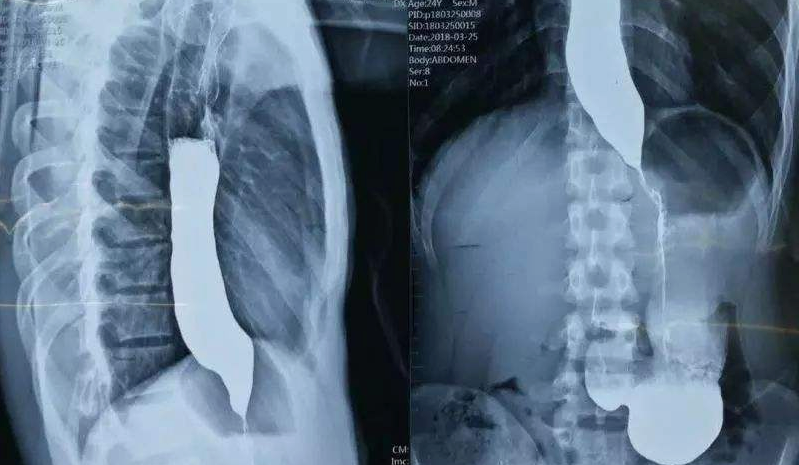

賁門失弛緩癥是一種食管動力障礙性疾病,其特點是食管體平滑肌無效蠕動和LES松弛障礙。臨床上出現(xiàn)吞咽困難等典型癥狀的患者可疑診為AC,再通過食管鋇劑造影、內(nèi)鏡檢查和食管測壓以確認診斷。HRM被認為是當前診斷AC的“金標準”。其治療方法主要有口服藥物治療、EBTI、PD、LHM、POEM等。上述治療多為姑息治療,短期改善癥狀效果較為明顯,但長期療效仍需大量臨床試驗加以評估。目前賁門失弛緩癥的西醫(yī)病因及具體機制仍未闡明,治療效果差強人意。本人以中醫(yī)理論為指導(dǎo)應(yīng)用藥物治療可以迅速緩解癥狀、根治賁門失弛緩癥,為賁門失弛緩癥的診治提供了新思路,給患者帶來了新的希望。